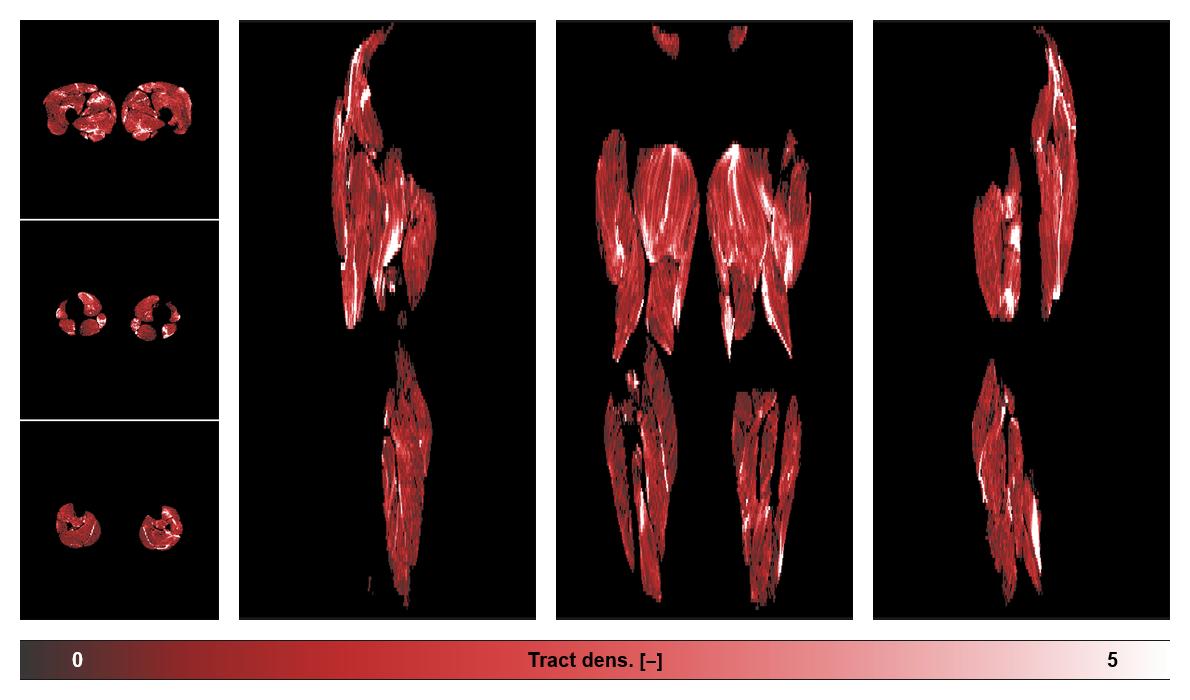

• Muscle fiber density map

Muscle fiber tract density map based on whole leg DTI based fiber tractography.